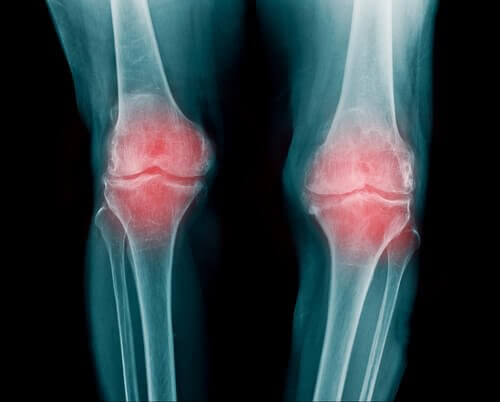

En led är ett område där två eller fler skelettben, alltså ben eller brosk, möts. De ger din kropp rörlighet. Enkelt förklarat får de dina armar, ben och rygg att böja och vrida sig. Mellan benen som leden består av finns det ett flexibelt, elastiskt material; ledbrosk. Brosk motverkar friktion mellan benen och fungerar som en barriär eller kudde.

Leden är omgiven av en ledkapsel som stöder uppbyggnaden. Det i sin tur stöds av ledband som hindrar dina leder från att lätt bli skadade.

- Reumatoid artrit är en inflammation av leden. Den kan påverka flera olika leder. Det är vanligast i fingrar, armar och knän.

- Personer med reumatoid artrit har nedsatt rörlighet. Efter krypandet kommer en värre smärta.

- Det inträffar när kalk ansamlas i leden. Sedan kommer krypande leder och försvagat brosk, vilket gradvis bryts ner och får smärtan att bli värre.

- Vi ser det oftast i handleder, fingrar och knän. Men det kan påverka andra leder också. Sjukdomen är förknippad med artros och sköldkörtelstörningar.